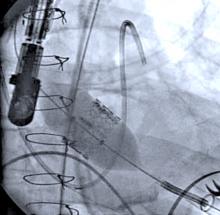

Early treatment of heart attack patients with an inexpensive beta-blocker drug called metoprolol, while in transit to the hospital, can significantly reduce damage to the heart during a myocardial infarction, according to clinical trial/study results published Oct. 1 in the journal Circulation. The study was a collaboration between Centro Nacional de Investigaciones Cardiovasculares Carlos III (CNIC) and Icahn School of Medicine at Mount Sinai.